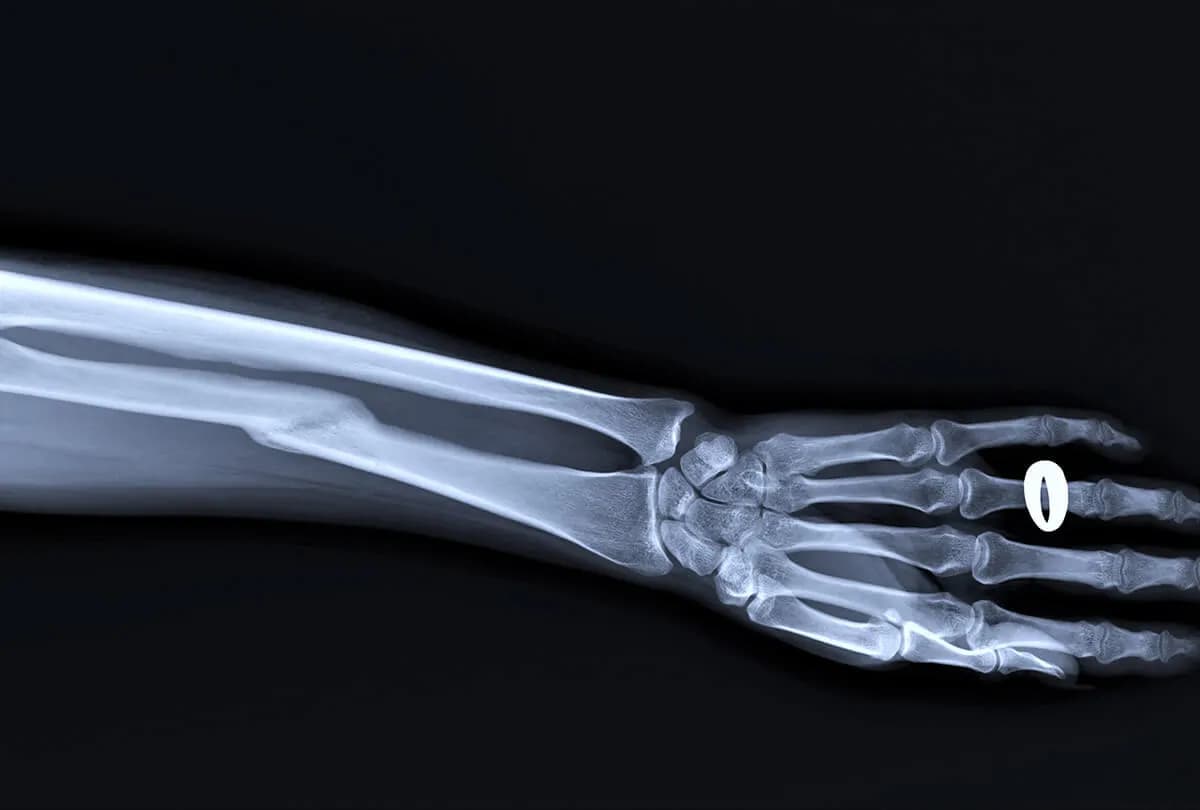

Wstępna diagnoza opiera się na badaniu fizykalnym i wywiadzie z pacjentem. Kluczowe jest wykonanie zdjęcia RTG, które potwierdza złamanie i określa stopień przemieszczenia. W niektórych przypadkach stosuje się też tomografię komputerową dla dokładniejszej oceny urazu.

Rodzaje złamań kości promieniowej

| Typ złamania | Złamanie Collesa | Złamanie Smitha |

| Opis | Odłam przemieszczony do tyłu | Odłam przemieszczony do przodu |

| Charakterystyczne cechy | Typowe dla upadku na wyprostowaną rękę | Rzadsze, często wynik uderzenia w tył ręki |

Istnieją również inne typy złamań, jak złamanie Bartona czy złamanie die-punch. Ich klasyfikacja zależy od linii pęknięcia i stopnia uszkodzenia stawu.